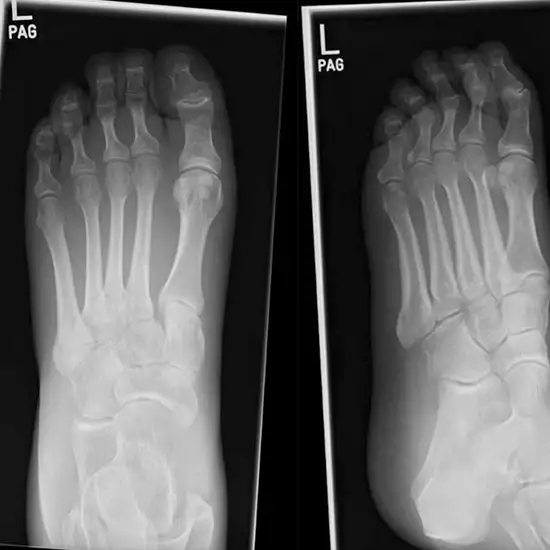

The X-Ray of both feet AP (Anteroposterior) and LAT View is used to see the bones of the feet, including the ankle bones (tarsal bones), the front end of the feet (metatarsal bones), and toes (phalanges), as well as the soft tissues (skin and muscles) around them.

The doctor prescribes this test to detect any broken or fractured bones in the foot and monitor the bone's healing after it has been set.

• To diagnose broken or shattered foot bones and keep an eye on how they heal.

• To find out if someone has an infection, osteoporosis, bone problems, or arthritis (inflammation of the joints).